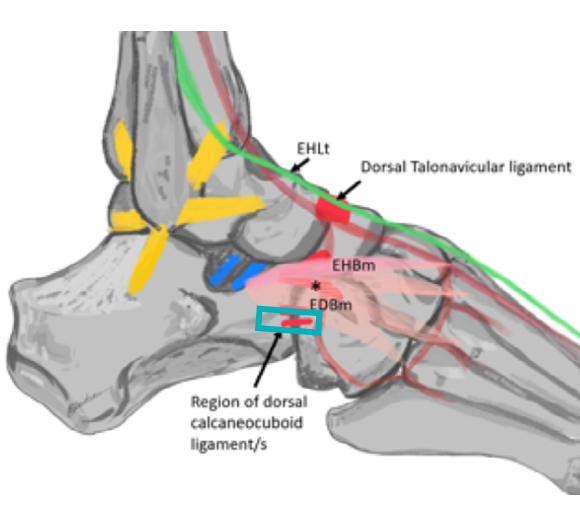

좌측 모식도 @ DOI: 10.1002/sono.12300 / 우측 초음파 영상은 직접 스캔했습니다

민트색 박스로 표시한 부위에

프로브를 댄 영상입니다.